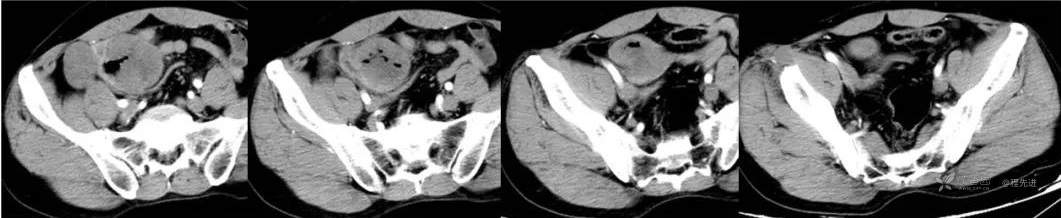

延迟期

冠状位